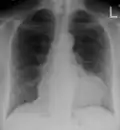

Ultrasounds showing a pericardial effusion in someone with pericarditis

-

A pericardial effusion as seen on CXR in someone with pericarditis

The diagnosis of tamponade can be confirmed with trans-thoracic echocardiography (TTE), which should show a large pericardial effusion and diastolic collapse of the right ventricle and right atrium. Chest X-ray usually shows an enlarged cardiac silhouette ("water bottle" appearance) and clear lungs. Pulmonary congestion is typically not seen because equalization of diastolic pressures constrains the pulmonary capillary wedge pressure to the intra-pericardial pressure (and all other diastolic pressures).